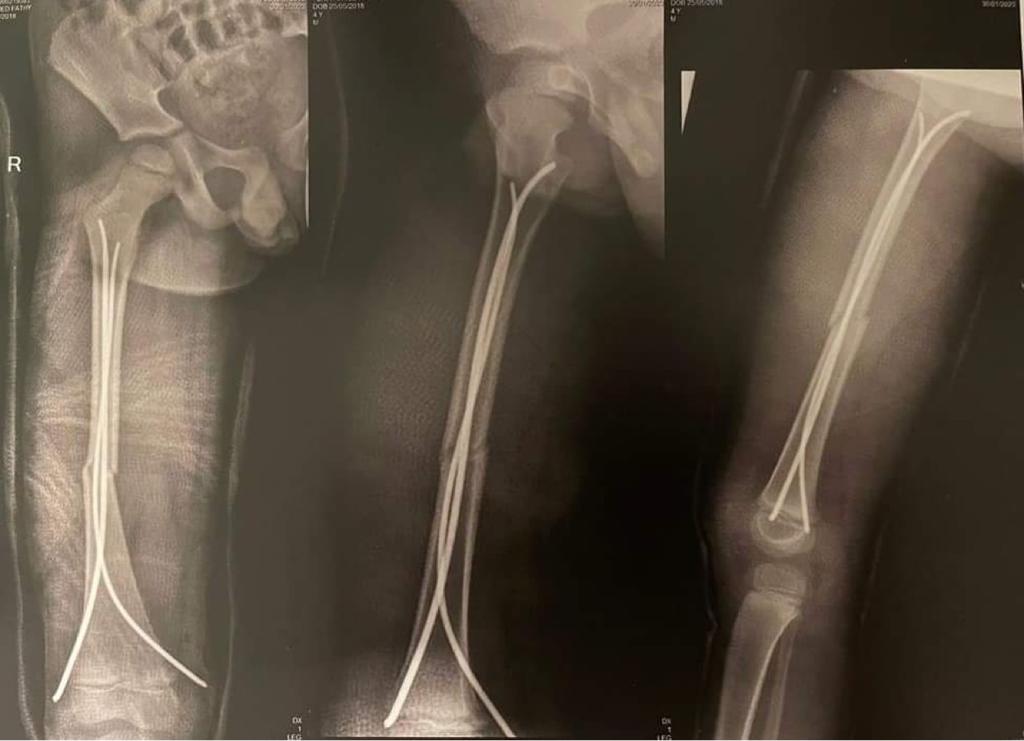

وقال والد الطفل أحمد فتحي لـ القاهرة 24: أصيب الطفل في كسر في الفخذ، وأجريت له عملية تركيب مسامير، وسيبدأ الطفل في رحلة العلاج الطبيعي، وبعد 4 شهور سيتم إجراء عملية أخرى له.

وأخبرت المستشفى والدة الطفل أنه مصاب بكسر في عظمة الفخذ، ويحتاج إلى عملية جراحية، ومن بعدها علاج طبيعي ويحتاج إلى عملية أخرى.